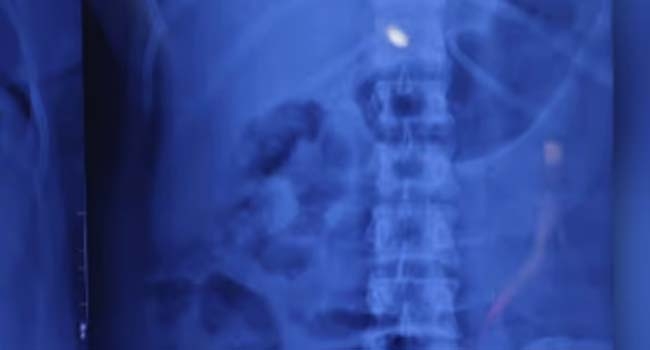

പെൺകുട്ടികളില്ലെന്നും കുഞ്ഞുപെൺകുട്ടികളെ വലിയ ഇഷ്ടമെന്നും പറഞ്ഞ് സമീന മോഷണം ആസൂത്രണം ചെയ്തു. ഇതിനിടയിൽ കുഞ്ഞ് ധരിച്ചിരുന്ന സ്വര്ണമാല കാണാതായി. സമീനയുടെ കൈവശവും മാല കണ്ടെത്താൻ കഴിഞ്ഞില്ല. ഒടുവിൽ സംശയം തോന്നി സമീനയെ തടഞ്ഞു വെച്ച് ചോദ്യം ചെയ്തപ്പോഴാണ് മാല വിഴുങ്ങിയ കാര്യം വ്യക്തമായത്. തുടര്ന്ന് പൊലീസിൽ വിവരം അറിയിക്കുകയായിരുന്നു. തുടര്ന്ന് ഇക്കാര്യം സ്ഥിരീകരിക്കാനായി പൊലീസ് സമീനയെ സ്കാൻ ചെയ്തു.

തുടര്ന്ന് വയറ്റിൽ സ്വര്ണമാല ഉണ്ടെന്ന് ഉറപ്പാക്കി. പിന്നാലെയാണ് മാല പുറത്തുവരുന്നതിനുള്ള കാത്തിരിപ്പ് തുടങ്ങിയത്. ആഭരണം വീണ്ടെടുക്കാൻ അടവുകൾ പലതും പൊലീസ് പയറ്റിയെങ്കിലും ഫലം കാണാൻ കഴിഞ്ഞില്ല. അതിനിടെ സമീനയുടെ അറസ്റ്റ് രേഖപ്പെടുത്തി കോടതിയിൽ ഹാജരാക്കി. തുടര്ന്ന് അഞ്ചു ദിവസത്തെ പൊലീസ് കസ്റ്റഡിയിൽ വാങ്ങി. തൊണ്ടി മുതൽ കണ്ടെത്താനുള്ള ശ്രമത്തിലാണ് പൊലീസ്. ഇതിന്റെ ഭാഗമായാണ് സമീനയെ കോഴിക്കോട് മെഡിക്കൽ കോളേജ് ആശുപത്രിയിലേക്ക് മാറ്റിയിരിക്കുന്നത്.